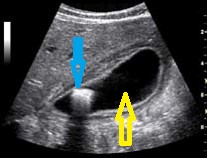

Imagen A.

En la imagen A tienes que decir qué aspecto ecográfico tiene la estructura que marca la flecha azul:

1. Hiperecogénico

2. Isoecogénico

3. Anecoico

4. Hipoecogénico.

En la imagen A tienes que decir qué aspecto ecográfico tiene la estructura que marca la flecha amarilla: